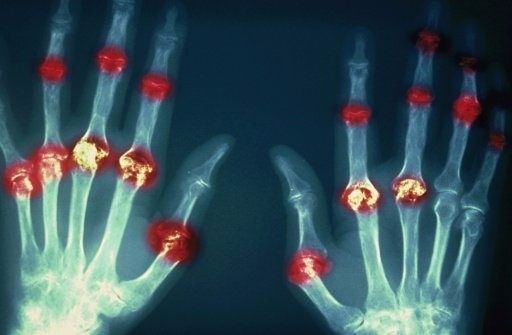

?類風濕關節(jié)炎

類風濕關節(jié)炎是一種高度致殘的自身免疫性疾病,發(fā)病十年的患者中至少有50%的人失去勞動能力。

類風濕關節(jié)炎©Health Same of Flickr

1977年,Baldwin在用骨髓干細胞移植治療再生障礙性貧血的過程中,意外發(fā)現(xiàn)患者的類風濕關節(jié)炎得到緩解。

2004年,歐洲骨髓移植和抗風濕病聯(lián)盟對60例類風濕病關節(jié)炎移植患者進行回顧性分析,這些患者的關節(jié)破壞都達到不可修復程度,生活不能自理,通過干細胞移植治療后,67%的患者得到明顯緩解。

我國國內(nèi)多家醫(yī)院已開展了干細胞治療類風濕性關節(jié)炎的臨床研究。首例自體干細胞移植治療類風濕關節(jié)炎在北京協(xié)和醫(yī)院完成。經(jīng)過5個月隨訪,這些經(jīng)常規(guī)藥物治療失敗且病情發(fā)展迅速的患者,在接受干細胞移植治療后,癥狀均獲得改善,關節(jié)腫脹消失,各項檢查指標恢復正常。

解放軍323醫(yī)院2011年的一項臨床研究中,27位患者(對照組)只使用藥物治療;另外153位患者(細胞治療組)在藥物治療的基礎上進行臍帶間充質(zhì)干細胞輸注。結果顯示,治療組DAS28、HAQ 評分、ACR20較對照組下降明顯(分值越低,療效越好),Th1/Th2趨于平衡、Treg升高與臨床實驗指標及癥狀的緩解直接相關。